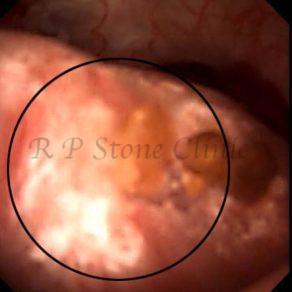

These images are taken as snap shots from the video recording of RIRS Surgery done at our hospital. These are Randall’s Plaques seen with Digital FLEX XC & Digital FLEX XC S. The cream or whitish patches are seen on the tips of RENAL PAPILLAE as seen in images below.

Randall’s Plaques may lead to the formation of Stones.

Those kidney stone patients who have Randall’s Plaques in their kidneys are more likely to form stones again (Recurrent Stones).